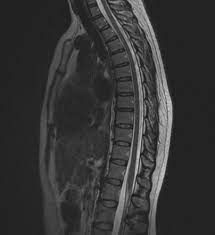

Thoracic Pain

The thoracic part of the spine is located in the 'middle' part of your back (in between the shoulder blades) and is formed of 12 vertebrae with a disc that resides in-between each one.

The design of the thoracic vertebrae differ to that of the cervical and lumbar region to provide muscular attachments for the numerous muscle groups that run past and through this area plus provide attachments for the 12 ribs. As a result, this part of our backs is stiff and rigid, with little movement provided except for the upper thoracic which do participate in rotation of the neck.